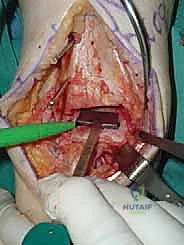

4. وضع أدلة القطع (Jig Placement and Alignment)

تعتمد دقة الجراحة على المحاذاة الصحيحة. يتم استخدام أجهزة توجيه متطورة (Jigs) تثبت على عظمة الساق باستخدام دبابيس معدنية. يتم التحقق من صحة الزوايا والمحاور باستخدام جهاز الأشعة السينية المباشر داخل غرفة العمليات (C-arm Fluoroscopy). يضمن الدكتور هطيف أن يكون القطع موازياً للأرض تماماً عند وقوف المريض.

5. القطع العظمي الظنبوبي (Tibial Bone Cut)

باستخدام منشار جراحي دقيق التذبذب، يتم إزالة شريحة رقيقة جداً (بضعة مليمترات) من السطح السفلي التالف لعظمة الظنبوب. يتم القطع بحذر شديد لتجنب إصابة الأوتار الخلفية أو الأوعية الدموية.

6. القطع العظمي الكاحلي (Talar Bone Cut)

بشكل مشابه، يتم توجيه دليل القطع نحو عظمة الكاحل (Talus) وإزالة السطح الغضروفي التالف وت